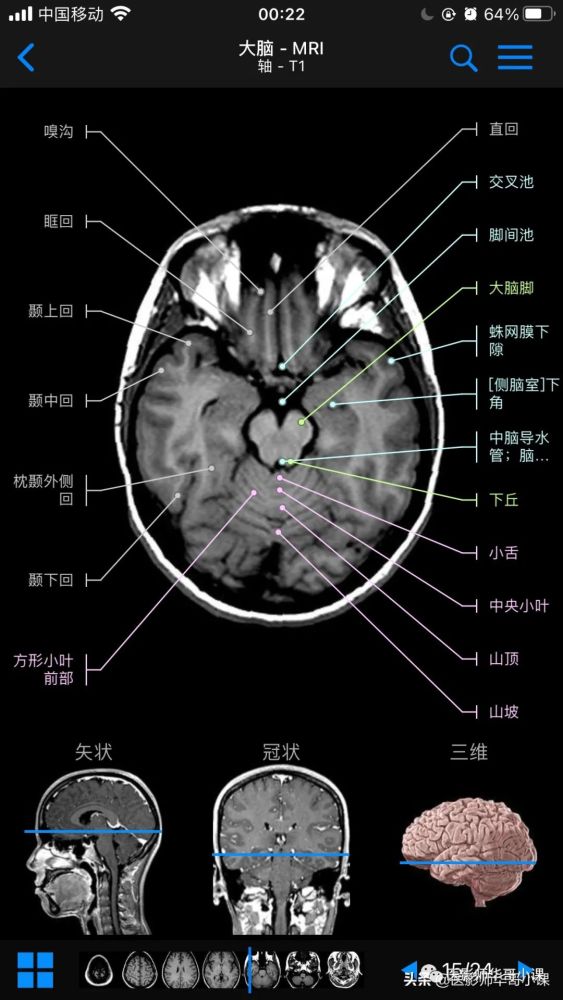

高清mri图颅脑磁共振mri解剖

图片尺寸563x1000